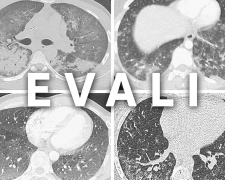

Що таке хвороба вейперів EVALI і чи дійсно вона вбиває